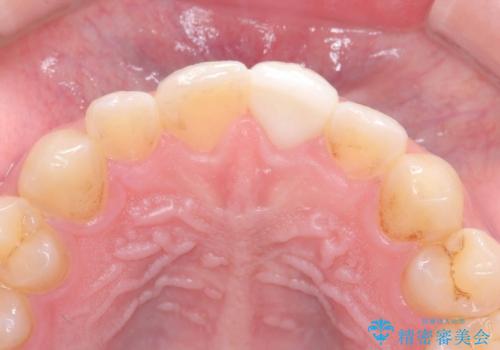

神経の状態が良好に保たれていることを確認した後、オールセラミッククラウンによる審美修復を行いました。

なお、最終補綴前にはオフィスホワイトニングを実施し、より自然で明るい仕上がりを得ることができました。

他院では「治療が難しい」と言われた患者様でしたが、当院で神経を残すことができ、見た目もきれいに仕上がったことで大変喜んでいただけました。